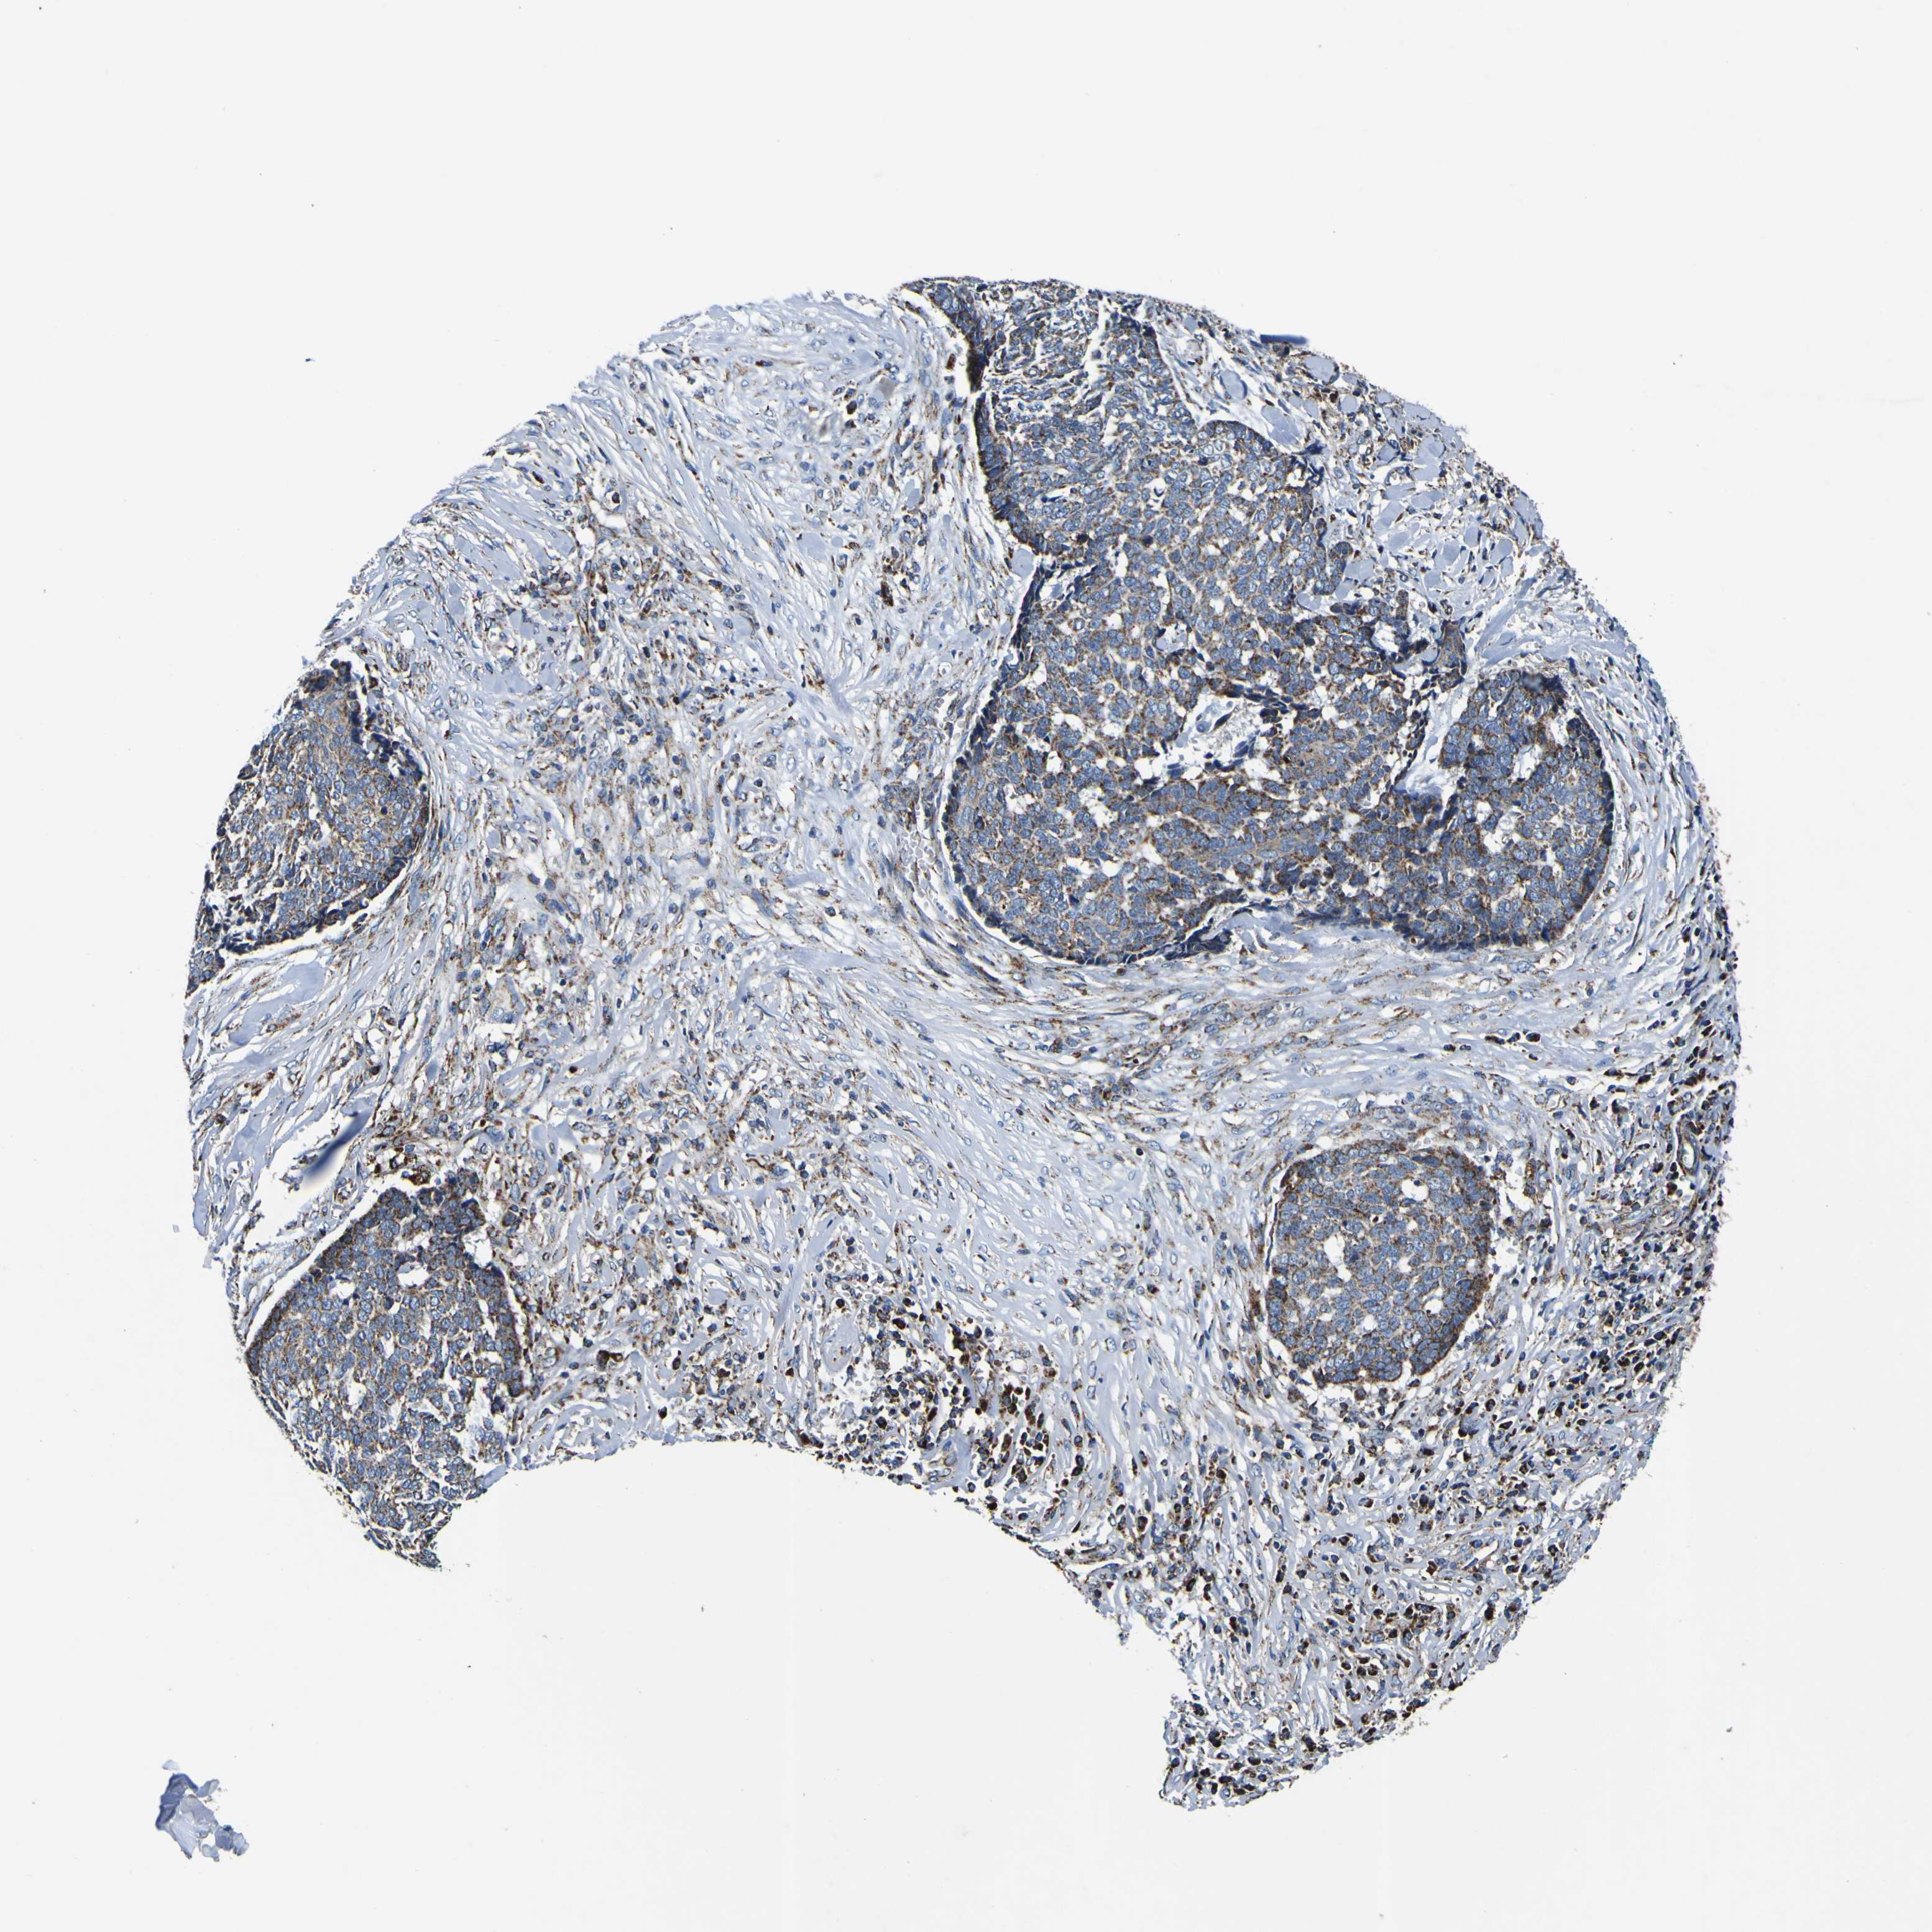

SKIN CANCER - Protein expressioni

A mouse-over function shows sample information and annotation data. Click on an image to view it in a full screen mode. Samples can be filtered based on level of antibody staining by selecting one or several of the following categories: high, medium, low and not detected. The assay and annotation is described here.

Each image is clickable and will lead to virtual microscopy that enables deeper exploration of all samples and also displays staining intensity scores, fraction scores and subcellular localization as well as patient and tissue information for each sample.

Antibody HPA012897

Basal cell carcinoma